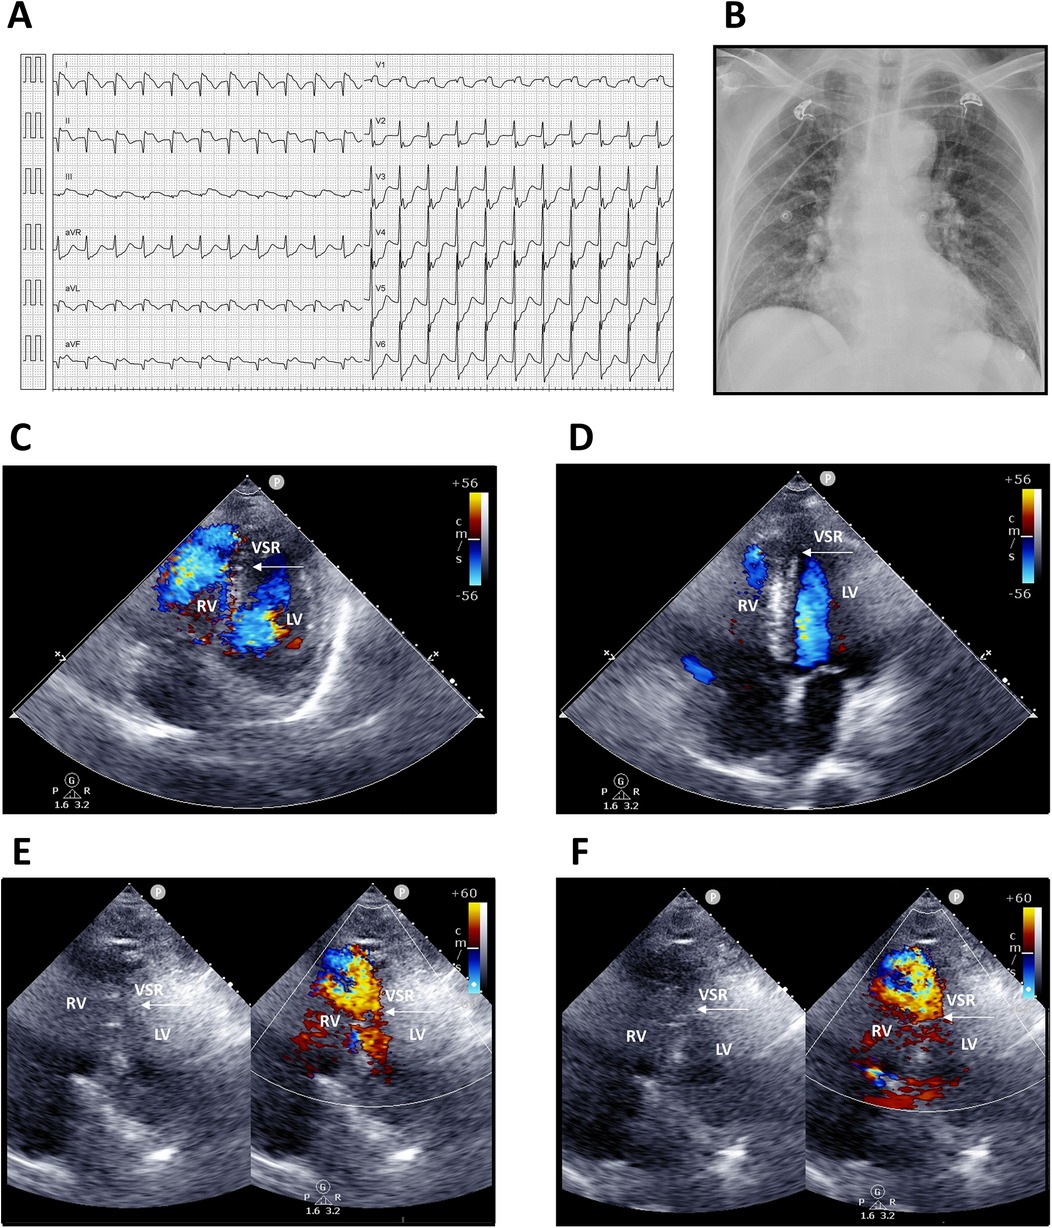

Upon arrival, he was conscious but in shock, with vital signs showing blood pressure 68/48 mmHg, heart rate 136 bpm, respiratory rate 20/min, and body temperature 35.4°C. Physical examination revealed a grade 3/6 pansystolic murmur along the left sternal border, with clear breath sounds. Laboratory findings demonstrated leukocytosis [white blood count (WBC) 12,150/µL, segmented neutrophils 95.8%] and elevated troponin-I (9.873 ng/mL). Electrocardiography showed supraventricular tachycardia, complete right bundle branch block (CRBBB); ST-segment elevation in leads I, II, and aVF (reversed arm leads); and ST-segment depression in V2–6 (Figure 1A). An acute inferior wall ST-elevation myocardial infarction was suspected. Chest radiography revealed right ventricular enlargement and pulmonary plethora (Figure 1B). Based on these findings, an acute inferior STEMI was diagnosed. Aspirin, ticagrelor, and intravenous heparin were administered.

Figure 1. Electrocardiography, chest radiography, and transthoracic echocardiography findings. (A) Twelve-lead electrocardiogram showing supraventricular tachycardia 130 bpm; incomplete right bundle branch block (ICRBBB); ST-segment elevation in leads I, II, and aVF (suspected reversed arm leads); and ST-segment depression in V2–6. (B) Chest radiograph demonstrating right ventricular enlargement and pulmonary arterial plethora. (C,D) Apical four-chamber views. (E,F) Modified apical four-chamber views with two-dimensional and color Doppler imaging, revealing a large rupture of the inferior–posterior interventricular septum (arrows) with a significant left-to-right shunt. LV, left ventricle; RV, right ventricle; VSR, ventricular septal rupture.

Transthoracic echocardiography suggested distal interventricular septum rupture with a left-to-right shunt (Figures 1C–F). Intravenous normal saline was given for hypotension, and the patient underwent emergency coronary angiography, which revealed total occlusion of the middle right coronary artery. Balloon angioplasty with bare-metal stenting was performed (Figures 2A,B; Supplementary Videos S1–S6). Left ventriculography confirmed a large rupture in the posterior inferior interventricular septum with significant left-to-right shunting (Figures 2C–F; Supplementary Videos S7, S8). VA-ECMO was initiated for hemodynamic stabilization, after which he was admitted to the intensive care unit (ICU). Informed consent for surgical intervention was obtained from his family.